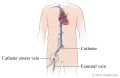

During an angiogram, the doctor will put a thin, flexible tube into a blood vessel in your groin or arm. This tube is called a catheter. The doctor guides the tube to the blood vessel that will be studied. Then a dye is injected through the tube to make the area easier to see. X-rays or pictures are taken of the area.

A round cylinder or rectangular box that takes the pictures during fluoroscopy will be moved above you. The fluoroscope will move under you during the test.

The place where the catheter will be inserted (in the groin or above the elbow) will be shaved and cleaned. Your doctor will numb the area with a local anesthetic. Then the doctor will put a needle into the blood vessel. A guide wire will be put through the needle into the blood vessel and the needle will be removed. The catheter will be placed over the guide wire and moved into the blood vessel. The catheter then will be guided through the blood vessels until the tip is in the area to be studied. Your doctor will use the fluoroscope to watch the movement of the catheter in the blood vessels.

When the catheter is in place, the dye is injected through it. You may be asked to take a breath and hold it for several seconds. Several X-ray pictures will be taken one after another. These will be available right away for your doctor to look at. You need to lie very still so the pictures are clear. More pictures may be taken.

After the test

The catheter is taken out after the angiogram, and pressure is put on the needle site for 10 to 15 minutes to stop any bleeding. A bandage or compression device is put on the site. This will prevent bleeding. You will be given pain medicine if you need it.

If the catheter was put in your groin, you will need to lie still and keep your leg straight for several hours. The nurse may put a weighted bag on your leg to keep it still. If the catheter was put in your arm, you may be able to sit up and get out of bed right away. But you will need to keep your arm still for at least 1 hour.